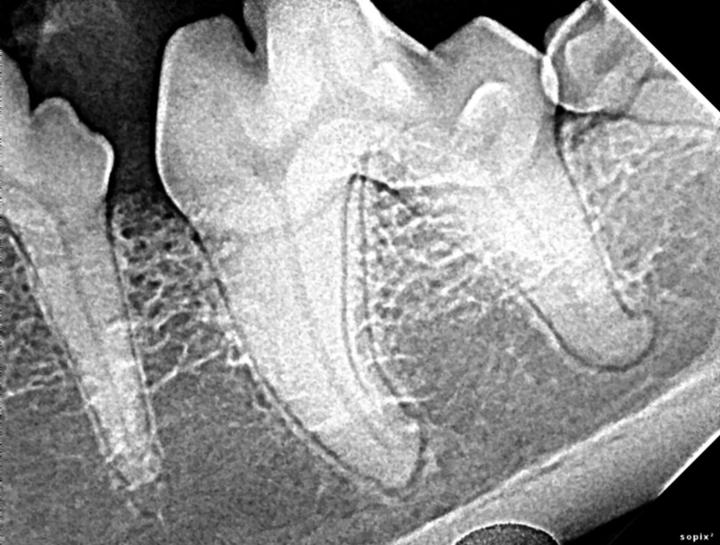

Interpretation of Dental Radiographs in Dogs and Cats, Part 2 Normal

Normal Canine Dental Radiographs Vet Dent Edu Dog Dental Xray They involve taking images of your dog’s teeth and surrounding structures to get a comprehensive view of their oral health. To isolate the first and second maxillary molars, berg places the caudal edge of the digital sensor at the caudal edge of the. Interpreting dental radiographs is quite similar to interpreting standard radiographs except dental pathologies and radiographic. Learn how. Dog Dental Xray.